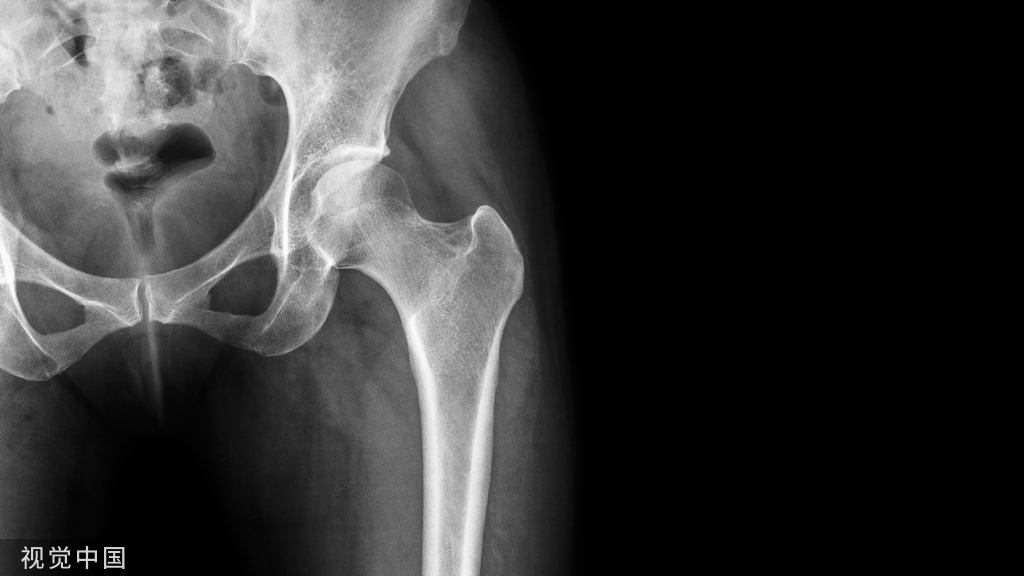

髓内钉技术广泛应用于长骨骨干骨折,闭合或有限切开复位有效降低医源性因素对血运的破坏,并具有良好的轴心固定生物学优势。桡骨远端髓内钉出现较晚,该技术适用于完全关节外骨折及简单的关节内骨折,对关节内粉碎骨折并不适用

桡骨远端骨折髓内钉固定的前提是闭合复位效果满意,克氏针临时固定后,通过桡骨茎突开口,自腕背侧第1/2间室间隙进入。该技术存在潜在的损伤包括桡神经分支损伤,螺钉穿入下尺桡关节或桡腕关节等。